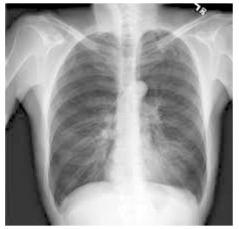

Um homem de 30 anos, previamente hígido, é admitido no pronto atendimento com queixa de febre e calafrios de início há 6 horas, seguidos de tosse seca. Está hemodinamicamente estável, com T =38 °C, eupneico, saturando 94% em ar ambiente. A radiografia de tórax mostra:

enunciado 500532-1